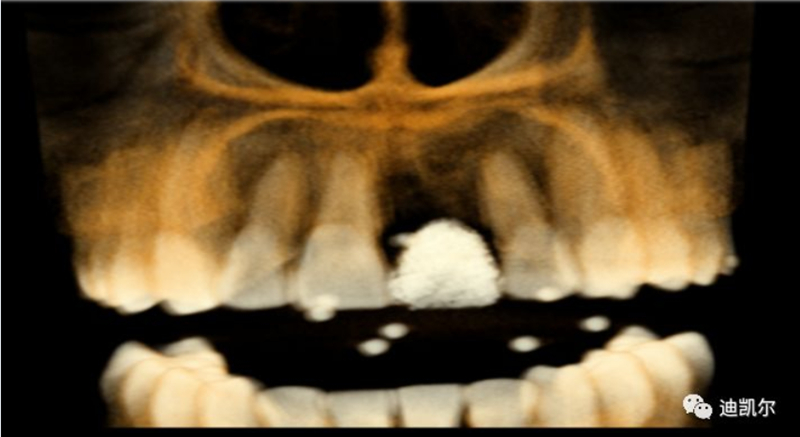

術(shù)前CBCT圖像和測量數(shù)據(jù)

*早期種植病例,頰側(cè)組織凹陷,肉眼可見骨缺損,需要種植同期GBR

*CBCT顯示骨缺損嚴重,種植窩洞制備困難,種植體很難獲得初期穩(wěn)定性